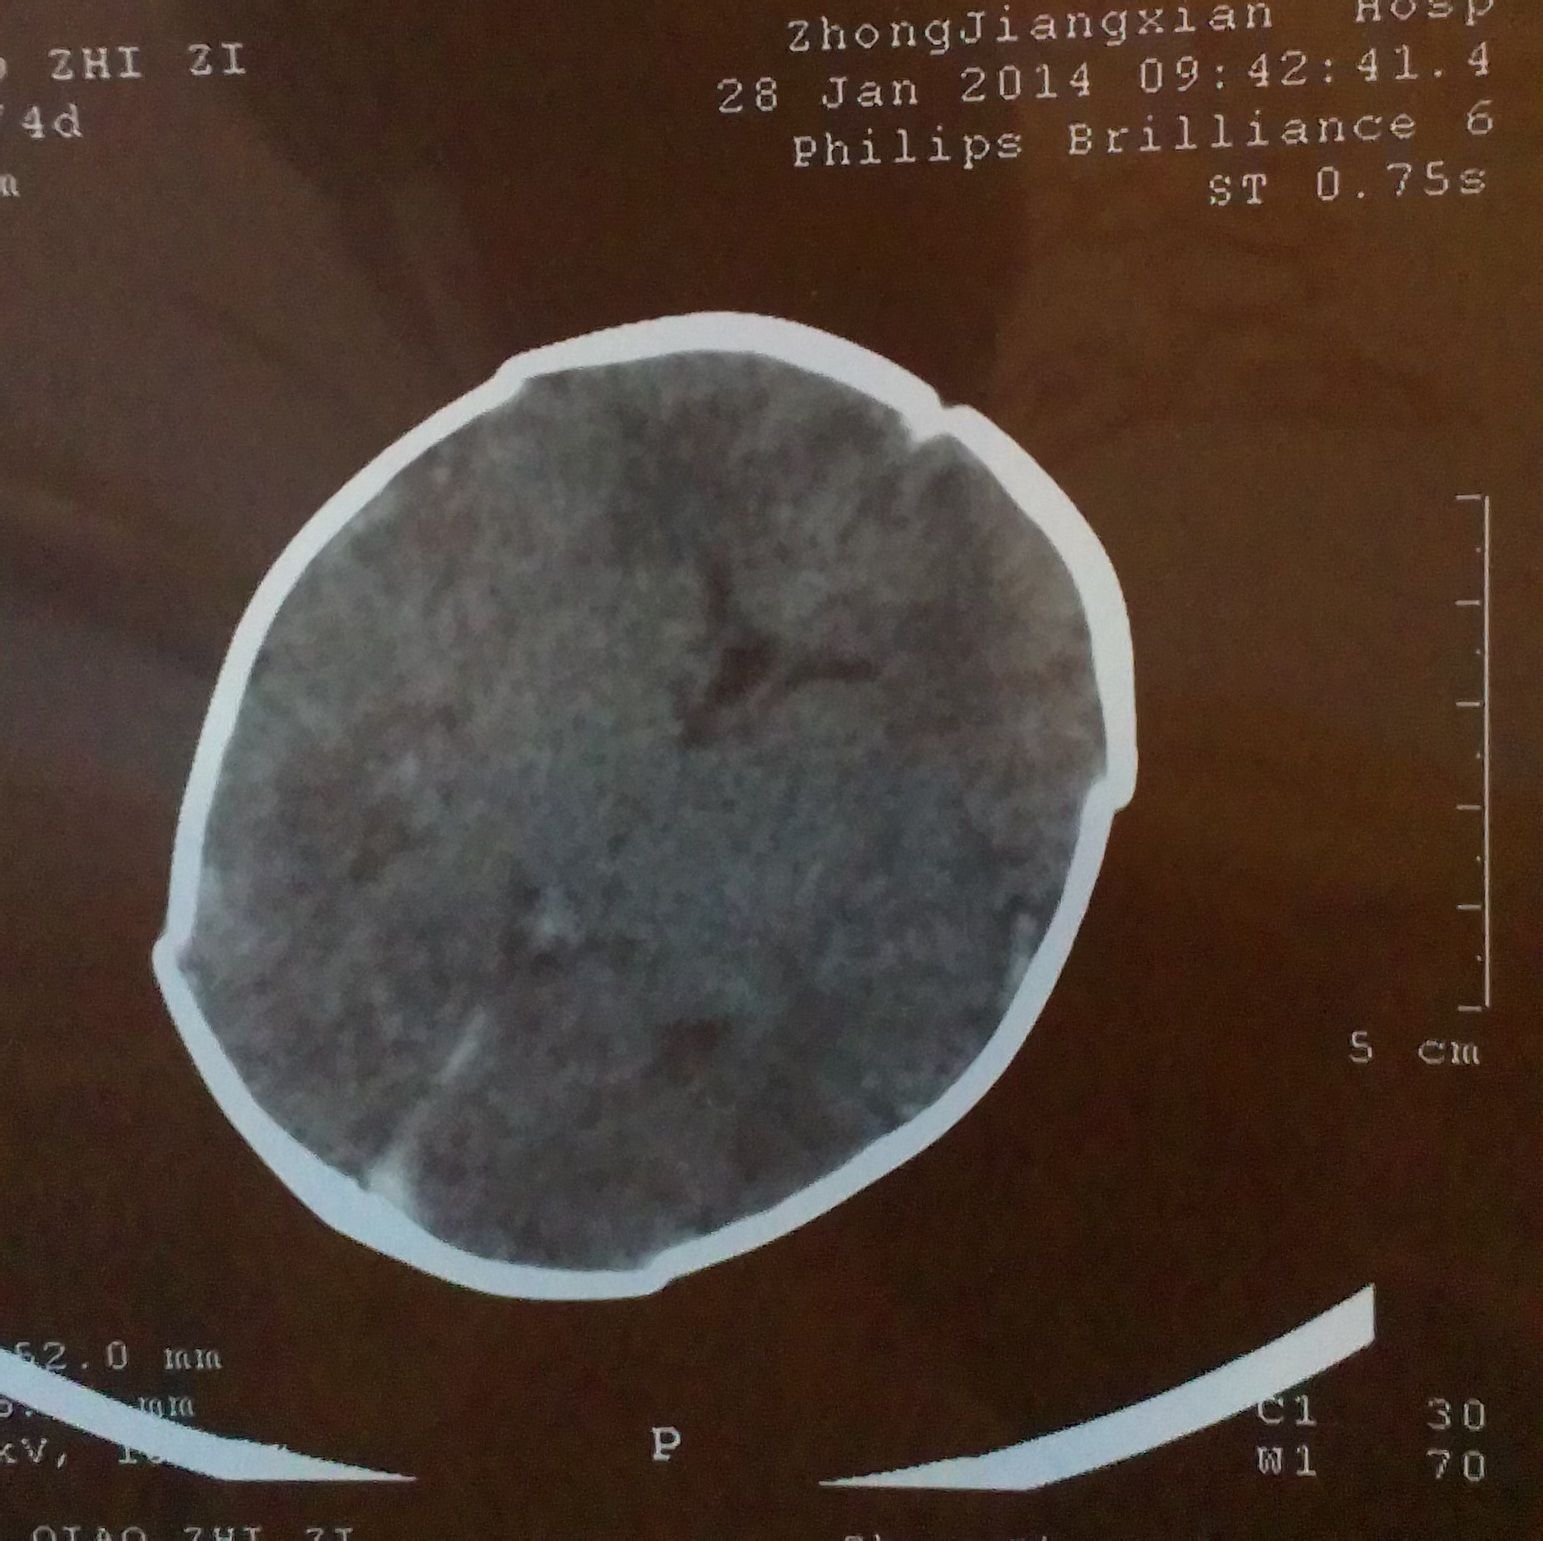

跪求能看懂脑部CT片子的专业人士帮忙,请帮我看一下,我小孩的脑部是什么问题 小孩是36周早产,这是 出生后第四天拍的CT片子,请帮我看一下,脑部有什么问题,严重吗?我应该怎么办,,,不胜感激,,,好人一生平安,感谢。 点击展开 匿名用户 2014-02-25 19:09 为您推荐: 其他回答 你好根据CT上的表现有蛛网膜下腔出血的表现,建议如果小孩子有不爱哭闹或者吃奶不好活动不好等情况及时复查一个颅脑CT或者MRI看看 丑梦月_TNVJ 2014-02-25 22:12 相关问题 宝宝是36周+2的早产儿,年龄25天了,医生要给宝宝照脑部CT,请问这么小照脑部CT 宝宝33周早产,已在保温箱5天了,检查均无问题(除脑部CT),现在每隔3小时吃一次,每次25mL 请问有谁的早产儿脑部发育不成熟用过申捷注射液?对大脑能够发育到什么程度?CT检测:脑部发育欠完善